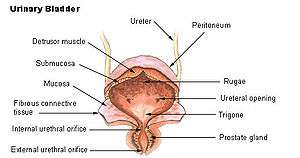

A healthy human male prostate is classically said to be slightly larger than a walnut. The mean weight of the normal prostate in adult males is about 11 grams, usually ranging between 7 and 16 grams.[6] A study stated that prostate volume among patients with negative biopsy is related significantly with weight and height (Body Mass Index), so it is necessary to control for weight.[7] The prostate surrounds the urethra just below the urinary bladder and can be felt during a rectal exam.

The secretory epithelium is mainly pseudostratified, comprising tall columnar cells and basal cells which are supported by a fibroelastic stroma containing randomly oriented smooth muscle bundles that's continuous with the bladder. The epithelium is highly variable and areas of low cuboidal or squamous epithelium are also present, with transitional epithelium in the distal regions of the longer ducts.[8] Within the prostate, the urethra coming from the bladder is called the prostatic urethra and merges with the two ejaculatory ducts.[9]

Benign prostatic hyperplasia

Benign prostatic hyperplasia (BPH) occurs in older men;[25] the prostate often enlarges to the point where urination becomes difficult. Symptoms include needing to urinate often (frequency) or taking a while to get started (hesitancy). If the prostate grows too large, it may constrict the urethra and impede the flow of urine, making urination difficult and painful and, in extreme cases, completely impossible.

BPH can be treated with medication, a minimally invasive procedure or, in extreme cases, surgery that removes the prostate. Minimally invasive procedures include transurethral needle ablation of the prostate (TUNA) and transurethral microwave thermotherapy (TUMT).[26] These outpatient procedures may be followed by the insertion of a temporary prostatic stent, to allow normal voluntary urination, without exacerbating irritative symptoms.[27]

The surgery most often used in such cases is called transurethral resection of the prostate (TURP or TUR). In TURP, an instrument is inserted through the urethra to remove prostate tissue that is pressing against the upper part of the urethra and restricting the flow of urine. TURP results in the removal of mostly transitional zone tissue in a patient with BPH. Older men often have corpora amylacea[28] (amyloid), dense accumulations of calcified proteinaceous material, in the ducts of their prostates. The corpora amylacea may obstruct the lumens of the prostatic ducts, and may underlie some cases of BPH.

Urinary bladder

Urinary bladder Structure of the penis